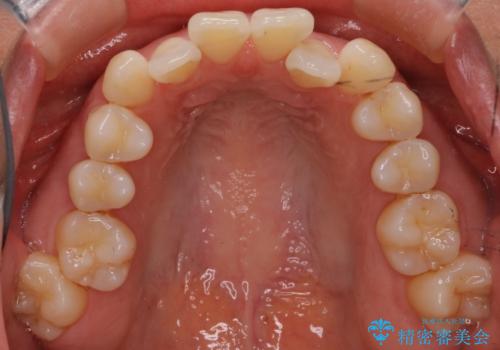

【抜歯ケース】前歯のガタガタをインビザラインで治療

- 前歯のガタガタを主訴に来院されました。

抜歯が必要なケースでしたが、インビザラインでの治療を希望されワイヤーを使用せずに治療を完了しております。